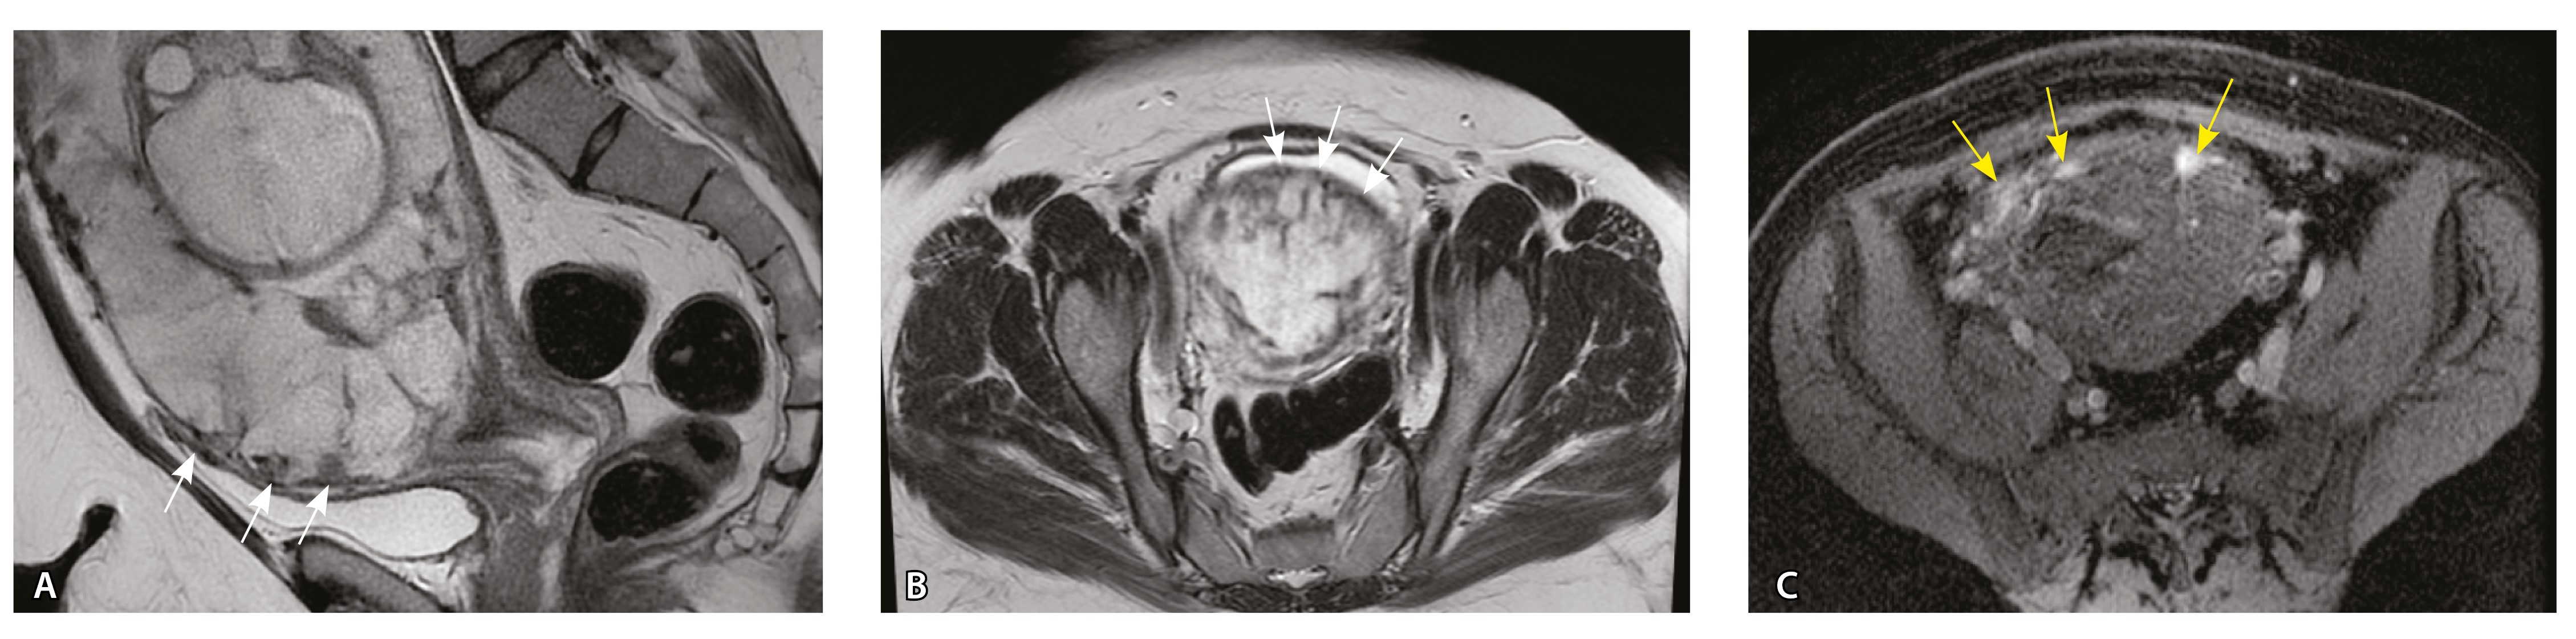

Сосуды 5-го типа. Наличие гиперваскуляризации за пределами матки по данным МРТ, на границе с мочевым пузырем с вовлечением его стенки, сосуды в области перешейка матки, параметрия, в том числе в сочетании с признаками фиброза, наличием рубцово-спаечных изменений и др. Можно предположить, что сосуды 5-го типа являются аналогом pl. рercreta PAS 3b, 3c (рис. 15).

Рис. 15. Беременность 34 недели, pl. percreta, PAS 3b по FIGO (A, Б), PAS 3c по FIGO (В). На магнитно-резонансных томограммах в режиме Т2-взвешенного изображения в сагиттальной (A, В) и аксиальной (Б) плоскостях определяется гиперваскуляризация в области выраженно истонченного нижнего маточного сегмента с распространением сосудов на заднюю стенку мочевого пузыря в области дна (белые стрелки), в область перешейка матки (желтые стрелки)

Данный вариант в патоморфологической картине наиболее сложен для оценки ввиду того, что такие структуры, как параметрий, перешеек матки, стенка мочевого пузыря, обычно не предоставляются в виде макропрепаратов, поэтому визуальные методы, в частности МРТ, могут с большей точностью оценить вовлеченность смежных структур. На микропрепаратах данный вариант инвазии плаценты сочетается с рубцово-спаечными изменениями задней стенки мочевого пузыря с нижним маточным сегментом (рис. 16).